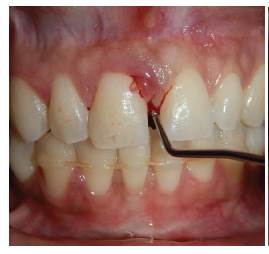

En el exámen estomatológico se observó lesión tumoral unilobular en el maxilar superior localizada a nivel de encía marginal vestibular por mesial de órgano dental 11, de base sésil, consistencia firme y blanda, de 3 mm de diámetro, de superficie eritematosa, con ligero sangrado al mínimo contacto, correspondiendo con las características clínicas descritas por Rebolledo y cols en 2015 11 (figura 1A). No se observa sobreinserción de frenillo labial superior que justifique la aparición de diastema entre los dos órganos dentarios anterosuperiores.

Se realizó evaluación de la condición de los tejidos periodontales a nivel de órgano dentario 11 mediante una sonda periodontal tipo Williams y se obtuvo profundidad de sondeo de 10 mm (figura 1B). Se evidencia margen gingival sin recesiones o hiperplasias en otras zonas; no se observa presencia de placa bacteriana abundante, cálculos supragingivales o caries que actúen como factor irritante asociado.